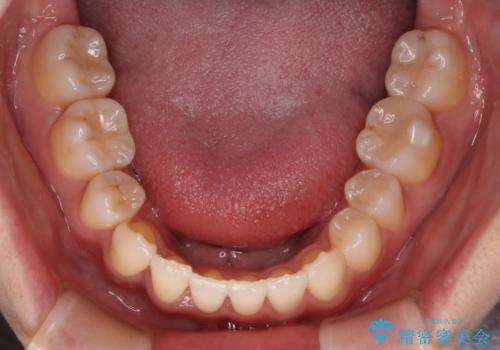

- 八重歯と叢生を主訴に来院されました。なるべく健康な歯を残したいという患者様の希望から、右側上下4番抜歯をしてワイヤー矯正する治療計画を立てました。

なるべく健康な歯を残したいという患者様の希望から、右側上下4番抜歯をして矯正しました。片側抜歯だったため、正中がズレないように気をつけながら治療を行いました。

正中もズレることなく主訴である八重歯と叢生を改善することができました。